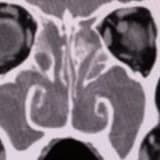

Baş dönmesi (vertigo) ile uyanmak veya aniden yerin ayağınızın altından kaydığını hissetmek oldukça endişe verici bir deneyim olabilir. Ancak çoğu zaman bu durum, iç kulaktaki kalsiyum kristallerinin yerinden oynamasından, yani tıp dilindeki adıyla BPPV (Benign Paroksizmal Pozisyonel Vertigo) durumundan kaynaklanır. Bu kristalleri tekrar ait oldukları yere oturtmak ve dengeyi geri kazanmak için evde uygulayabileceğiniz bilimsel yöntemler bulunmaktadır.